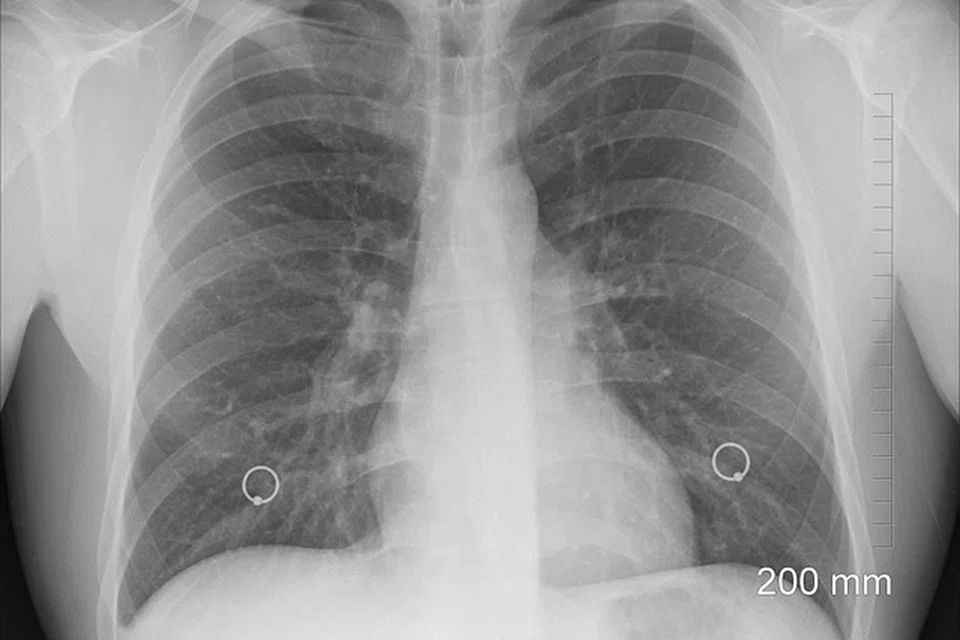

நுரையீரல் புற்றுநோயாளிகளில் அதிகமானோர் உயிரிழப்பதற்குக் காரணம், அவர்களில் முக்கால்வாசிப் பேருக்கு நோயின் மூன்றாம் அல்லது நான்காம் கட்டத்தின்போதுதான் பாதிப்பு அடையாளம் காணப்படுகிறது.

தற்போது நுரையீரல் புற்றுநோயாளிகளில் 68 விழுக்காட்டினருக்கு நோயின் தீவிரம் நான்காம் கட்டத்தில் உள்ளதாக தேசியப் பல்கலைக்கழக மருத்துவமனையின் நுரையீரல் சிகிச்சைப் பிரிவைச் சேர்ந்த பேராசிரியர் லீ பிங் கூறினார். அத்தகையோர் ஐந்து ஆண்டுகள் உயிர்வாழ்வதற்கான சாத்தியம் 20 விழுக்காடு மட்டுமே என்றார் அவர்.